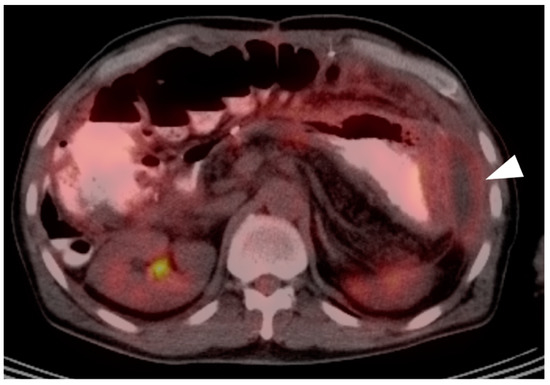

3. Gastrointestinal Stromal Tumor (GIST)